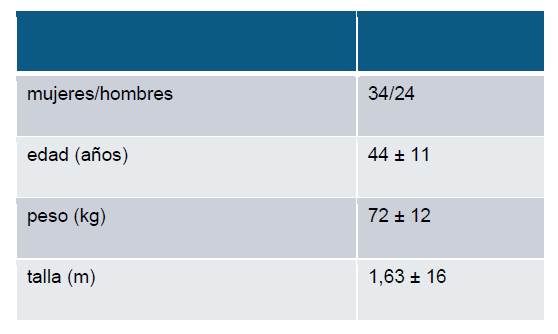

Se estudió un total de 52 pacientes (Tabla 1), en sólo 2 no hubo ventanas ecocardiográficas satisfactorias para poder ser incluidos en el estudio. La edad promedio fue de 44,8 ± 11 años.

Tabla 1: Características de la población